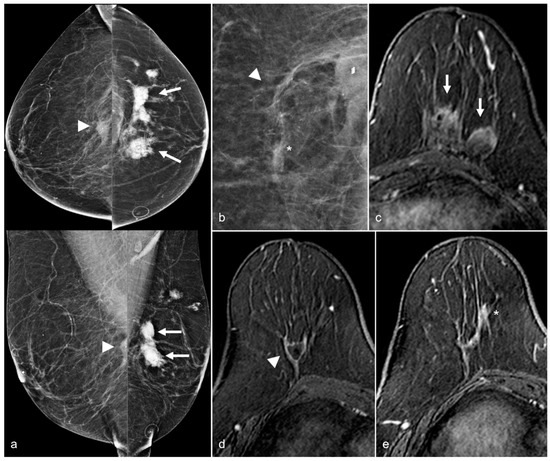

Figure 14. A 65-year-old woman with a history of a ruptured subglandular silicone implant. Screening mammogram (a) demonstrates very dense masses (arrows) in the left prepectoral region on the CC and the MLO views. Suspicious right breast calcifications (arrowhead) were biopsied with a biopsy clip seen in a hematoma in the right prepectoral region on the CC and MLO views. Pathology revealed ductal carcinoma in-situ. An additional biopsy was performed in the right breast for a small focal asymmetry (*) better seen on magnified CC view (b) and pathology demonstrated invasive ductal carcinoma. MRI demonstrates a T1 isointense peripherally enhancing silicone granuloma in the left breast prepectoral region ((c), arrows). In the right breast, a biopsy clip is seen within the biopsy cavity ((d), arrowhead). Anterior and inferior to this region (e), there is a linear non-mass enhancement. More anterior and medial to the non-mass enhancement, there is an enhancing mass (*), corresponding to the biopsy-proven invasive ductal carcinoma.